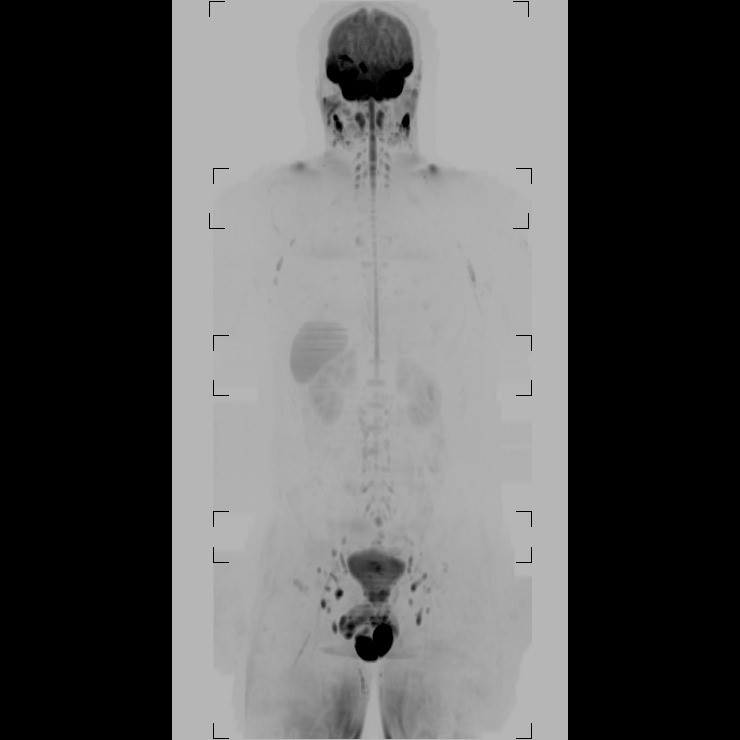

- Preventivní onkologický screening je zaměřen na odhalení bezpříznakového onemocnění, je složen ze specifických laboratorních odběrů, celotělového scanu magnetickou rezonancí a doplňujících vyšetření oddělení zobrazovacích metod. Vyšetření magnetickou rezonancí je vysoce moderní, neinvazivní celotělové vyšetření bez dávky záření, obsáhne oblast od hlavy do poloviny stehen. Laboratorní odběry zahrnují zejm. onkomarkery: celostní, prostatické, střevní a gynekologické (vaječníky + prsa). Odebírá se i FOB (okultní krvácení).